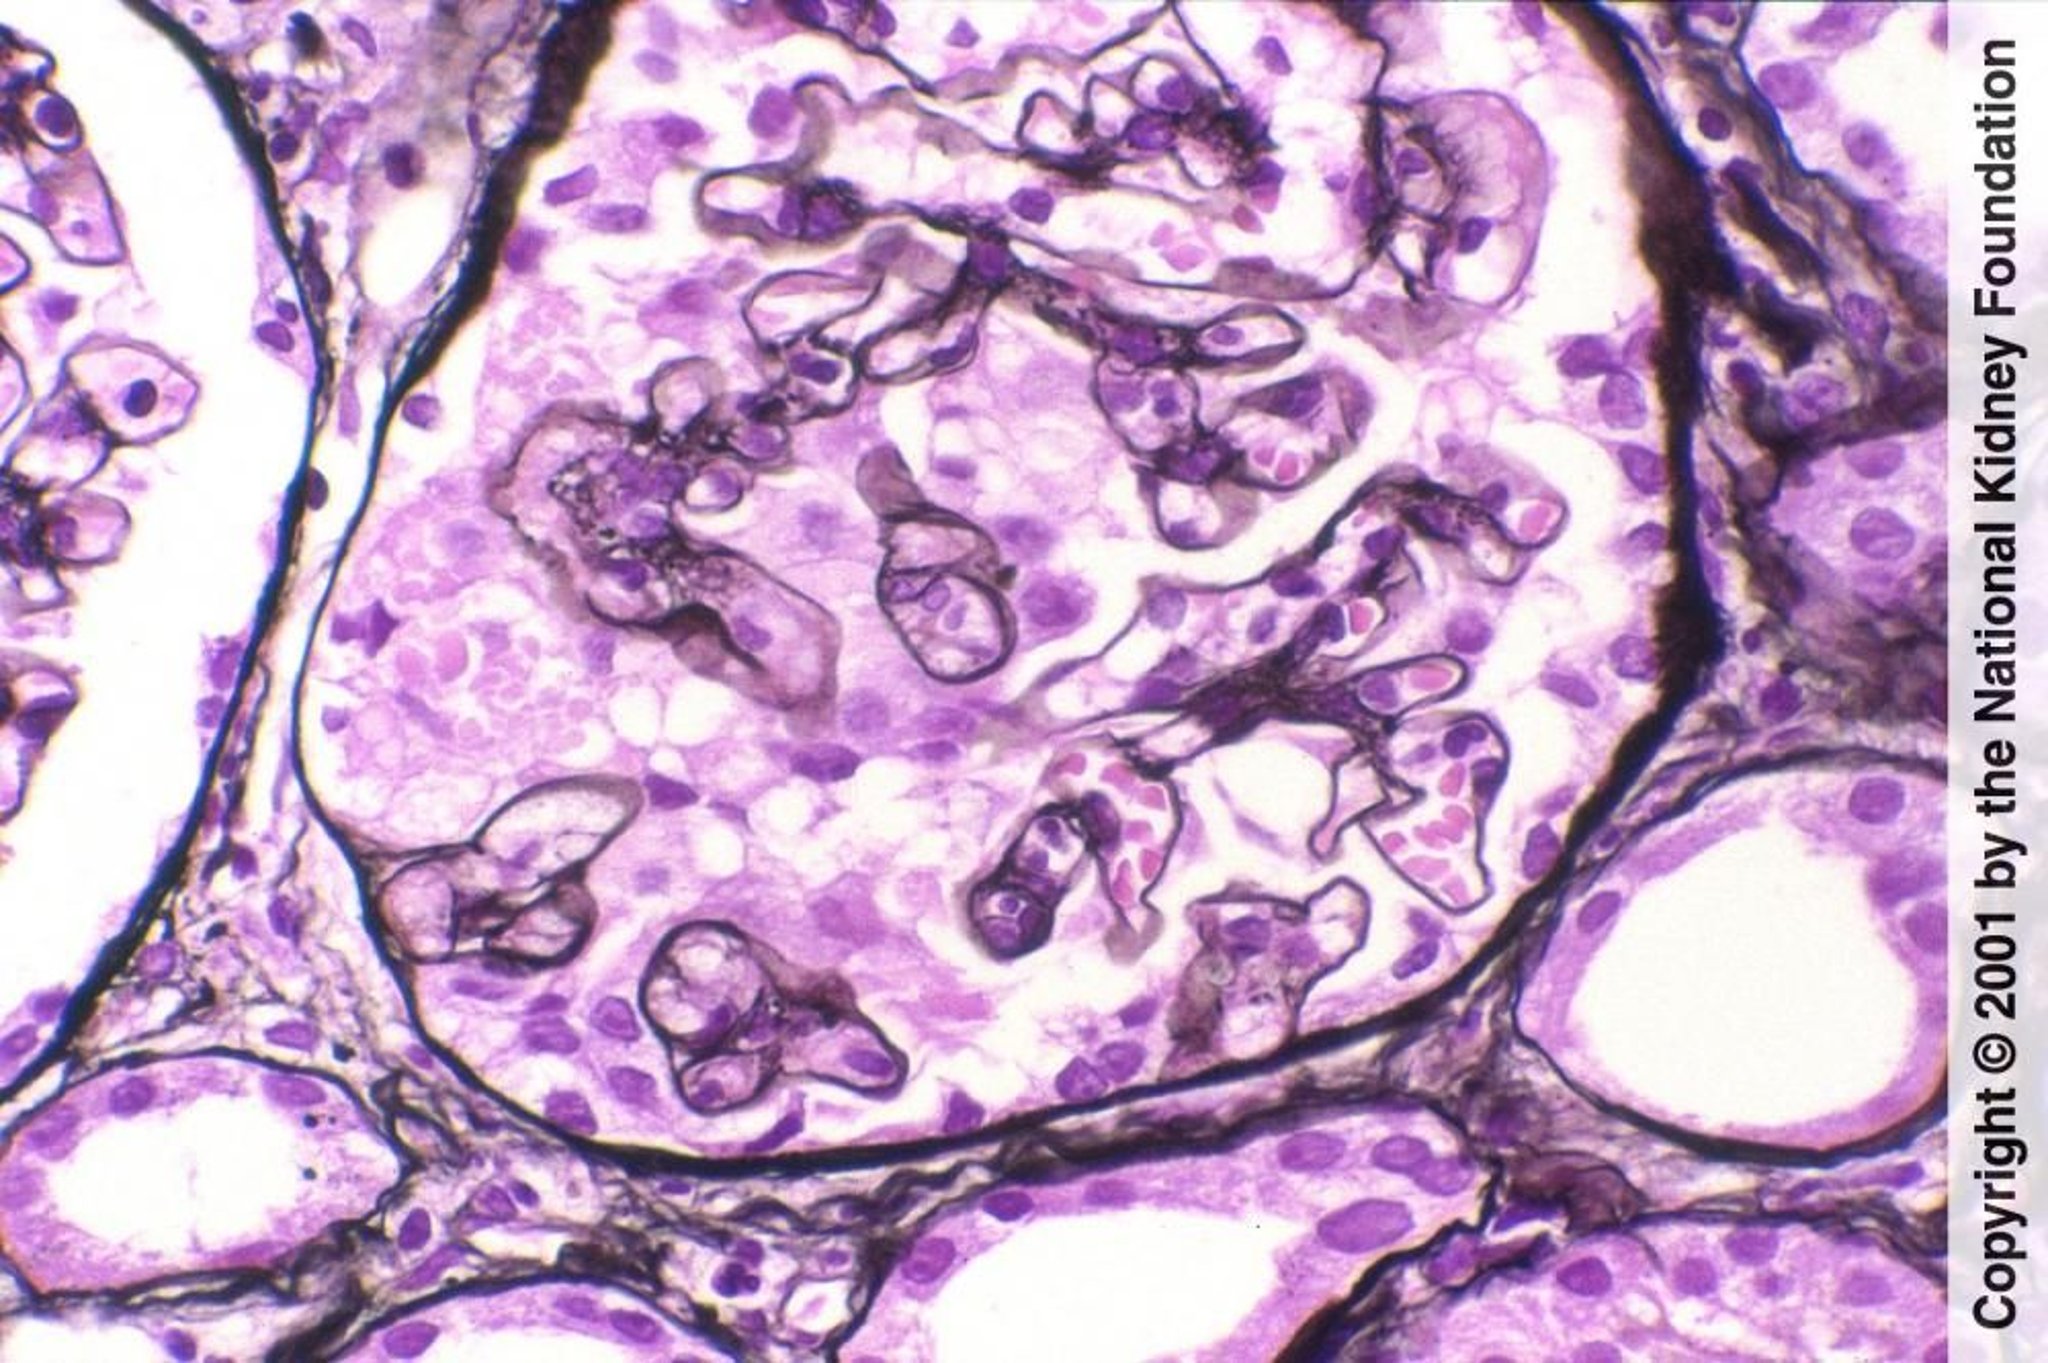

Collapsing Glomerulopathy

Le froissement ou l'effondrement de la pelote capillaire (touffe glomérulaire), accompagnés ici d'une dilatation microkystique des tubules, peuvent survenir en cas de glomérulosclérose segmentaire et focale ou de néphropathie associée au VIH et sont un marqueur pronostique défavorable (coloration de Jones à l'argent, ×400).

Image fournie par Agnes Fogo, MD, and the American Journal of Kidney Diseases' Atlas of Renal Pathology (voir www.ajkd.org).